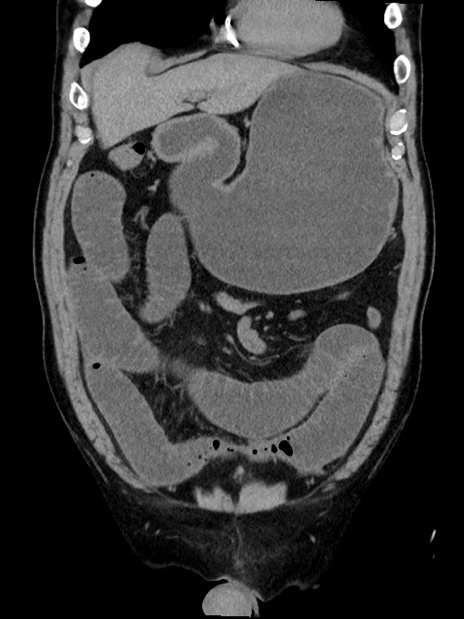

症例35(冠状断像)

【症例】70歳代 男性

【主訴】腹部膨満、嘔吐

【現病歴】昨日より腹部膨満感出現。本日増悪し、仙痛出現。嘔吐あり、受診。

【既往歴】糖尿病、胆摘後

【身体所見】BP 149/80mmHg、HR 74/min、BT 35.9℃、腹部:膨満、軟、圧痛なし。腸雑音減弱あり。上腹部正中切開瘢痕あり。

【データ】WBC 13500、CRP 1.72